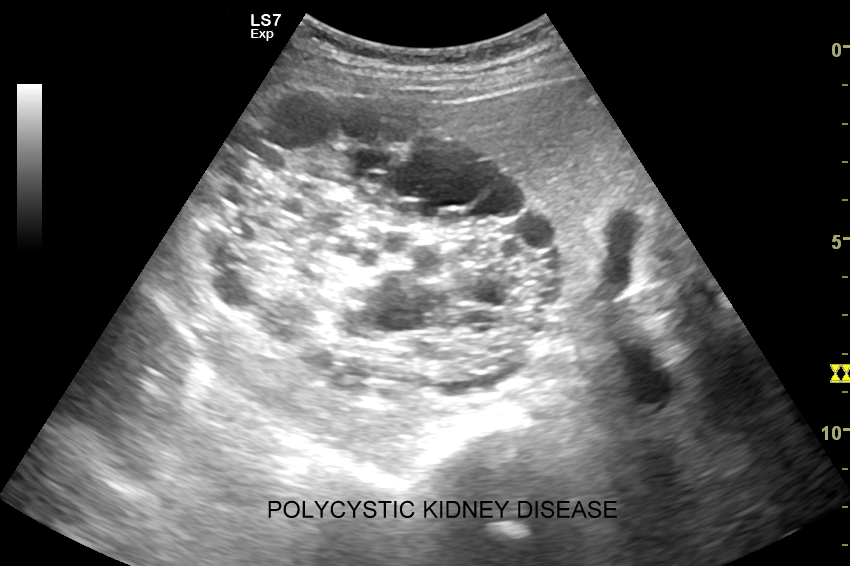

Inne wskazania do przeprowadzenia diagnostyki USG przepływów nerkowych obejmują ocenę funkcji nerek w przebiegu chorób ostrych oraz przewlekłych, takich jak nefropatia cukrzycowa, glomerulopatie, czy zapalenia kłębuszków nerkowych. Badanie USG Doppler wykonywane jest również przy podejrzeniu zakrzepicy żyły nerkowej i zespołu „dziadka do orzechów”; przy stwierdzeniu obecności żylaków powrózka nasiennego u mężczyzn; żylaków miednicy u kobiet; w sytuacjach, gdy podczas standardowego badania USG jamy brzusznej uwidoczniono patologię nerki (np. guz nerki, marskość); a także przy stwierdzeniu podwyższonych wartości parametrów nerkowych w badaniach laboratoryjnych (kreatynina, mocznik, cystatyna C, potas) oraz w ramach oceny USG nerki przeszczepionej.